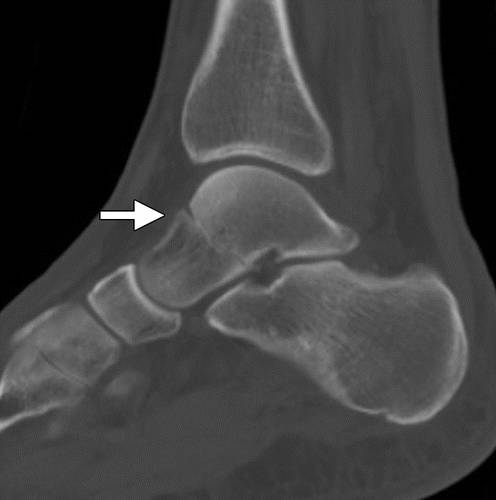

该分类系统是基于与垂直距骨颈骨折的关节排列不齐。 类型I是没有半脱位或脱位的距骨颈的无位移骨折(图5)。 这种类型的裂缝通常难以检测,因为垂直裂缝线可以平行于X射线束。 唯一的距骨血液供应通常涉及这种类型的损伤,都是来自于距骨颈的背侧方面进入椎间孔及近端进步进入人体血管。 剩余的两个血供血源得以保留。

图5 Hawkins-Canale I型距骨颈骨折。 踝关节的矢状CT图像显示通过距骨颈的非置换骨折(箭头)。 注意,骨折前面的后下方小关节面的下延伸,限定了距骨颈部位置。